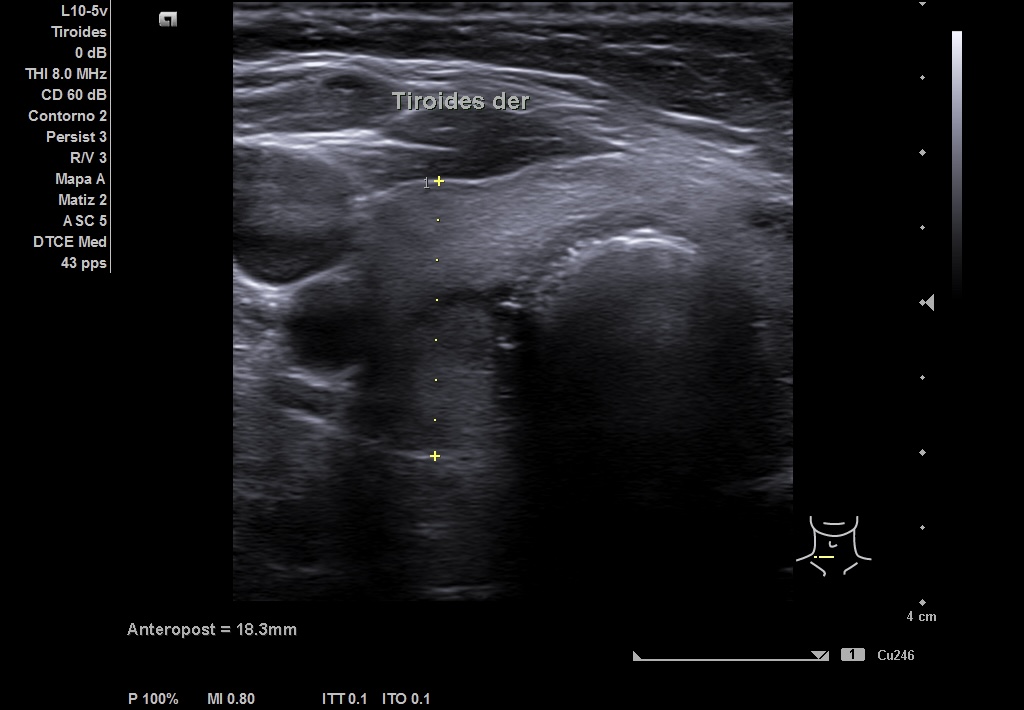

Se realiza ecografía en el Centro de Salud, en la que se objetiva en LTD un nódulo que impresiona de bilobulado, sólido, con una región caudal calcificada que no deja valorar su contenido y una parte superior isoecoica con alguna zona más hipoecoica. Diámetro antero-posterior (13 mm) mayor que el transversal (8 mm) y sagital (19 mm). Vascularización periférica. TIRADS 4-5.